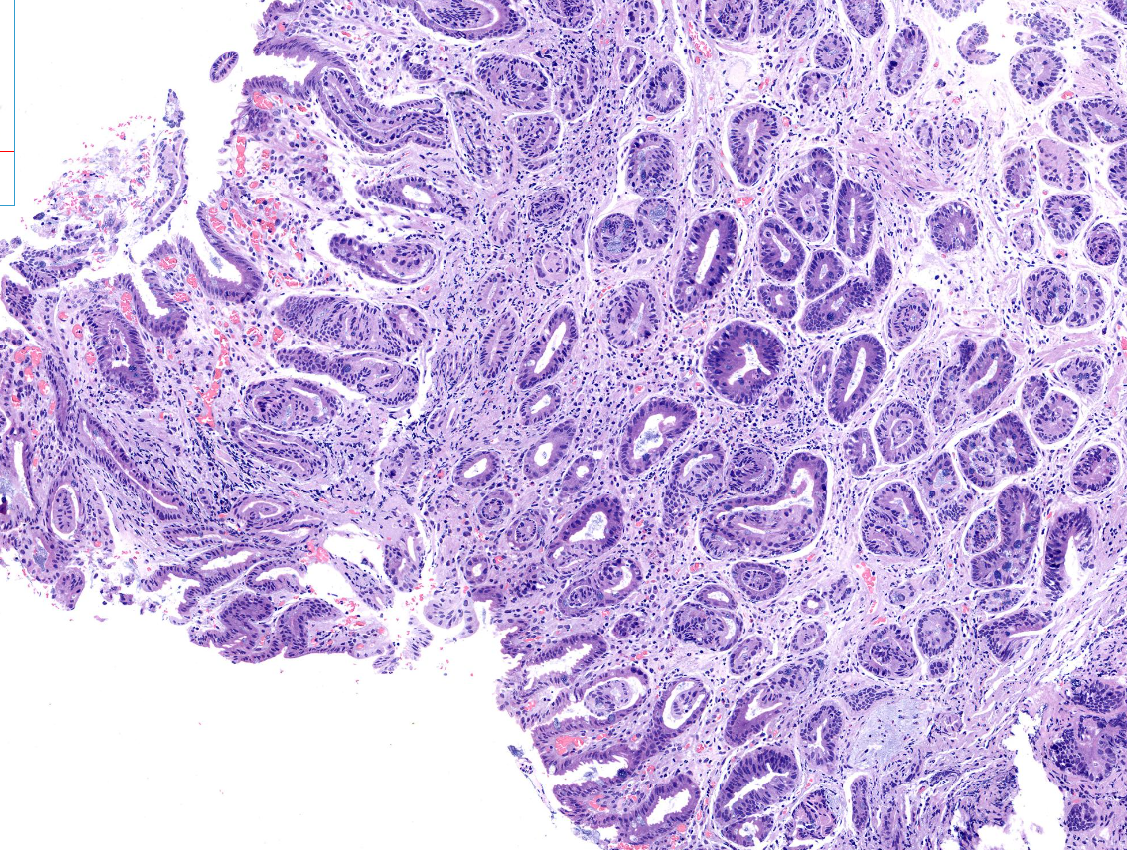

胃窦体交界表浅平坦病变

胃窦体交界活检

窦体交界表浅平坦病变1*1.2cm.

标记排除高级别

倾向炎症反应性增生

慢性炎症,伴有肠化。

高瘤

深切之后局灶高瘤

高级别

高瘤变。